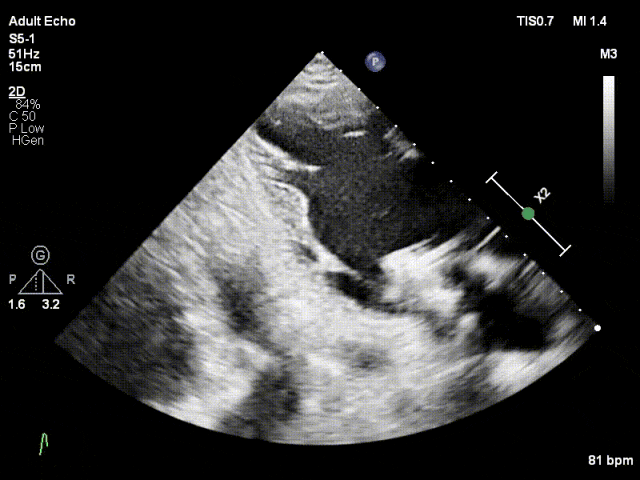

TTE下捕捞瓣叶

瓣叶捕获,Bouncing明显

缓慢关闭夹合角度至30°